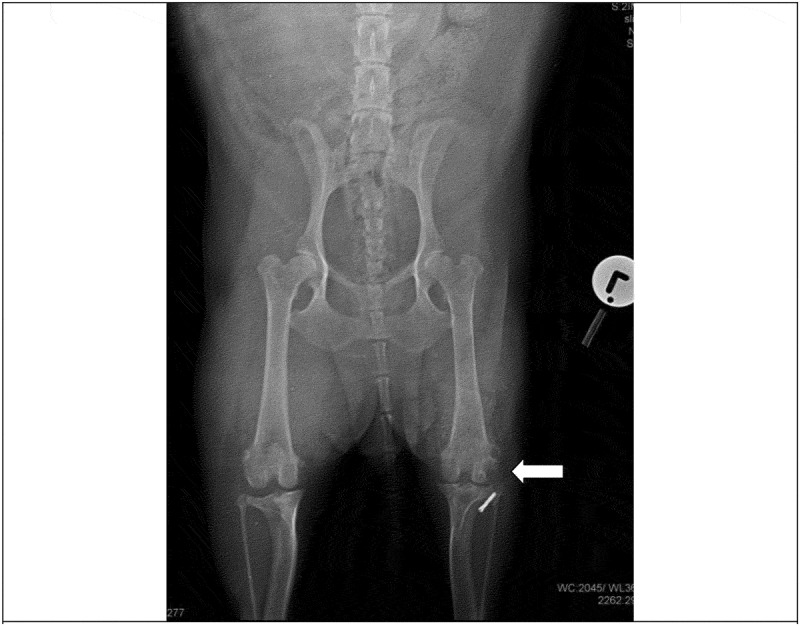

我们描述了一例慢性淋巴浆细胞性绒毛结节性滑膜炎(CLPVNS)与颅十字韧带(CCL)疾病相关的10岁绝育杰克罗素梗母狗。这只母狗被送到兽医诊所,患有严重的、非负重的、急性左后肢跛行。这只母狗先前曾使用外侧腓骨缝合(LFS)技术对同一关节的膝关节CCL疾病进行手术治疗。自治疗以来,患者有间歇性左后肢非负重性跛行史,可通过非甾体抗炎药(NSAIDs)治疗。触诊和操作受影响的膝关节引起剧烈疼痛。没有其他临床或矫形异常。受影响的膝关节的正交x线片显示中度退行性关节疾病和股骨外侧髁外侧和腓骨头部的溶骨性病变。从关节处抽吸的液体培养细菌生长阴性。细胞学结果怀疑为CLPVNS。探查性关节切开术、滑膜切除术、清创术及关节灌洗术。获得关节的骨和滑膜活检样本并提交实验室进行组织病理学确诊。细胞学初步诊断CLPVNS,活检标本病理证实。本病例报告强调了在伴有CCL疾病的跛行犬中检查CLPVNS的重要性,因为报告显示它被低估或误诊。

We describe a case of chronic lymphoplasmacytic villonodular synovitis (CLPVNS) associated with cranial cruciate ligament (CCL) disease in a 10-year-old spayed Jack Russell Terrier bitch. The bitch was presented to a veterinary clinic with severe, non-weight bearing, acute left hindlimb lameness. The bitch had previously been treated surgically for stifle CCL disease of the same joint, using the lateral fabellar suture (LFS) technique. Since the treatment, the patient had a history of intermittent left hindlimb non-weight bearing lameness that was manageable with nonsteroidal anti-inflammatory drugs (NSAIDs). Palpation and manipulation of the affected stifle elicited severe pain. There were no other clinical or orthopaedic abnormalities. Orthogonal radiographs of the affected stifle revealed moderate degenerative joint disease and osteolytic lesions on the lateral aspect of the lateral femoral condyle and the head of the fibula. A fluid aspirate from this joint was negative for bacterial growth on culture. Cytology results were suspicious for CLPVNS. Exploratory arthrotomy, synovectomy, debridement and lavage of the affected joint were performed. Bone and synovial membrane biopsy samples of the joint were obtained and submitted to a laboratory for a histopathological confirmatory diagnosis. CLPVNS was tentatively diagnosed by cytology, and confirmed by histopathology of biopsy samples. This case report highlights the importance of checking for CLPVNS in dogs with lameness associated with CCL disease, as reports show it to be underreported or misdiagnosed.